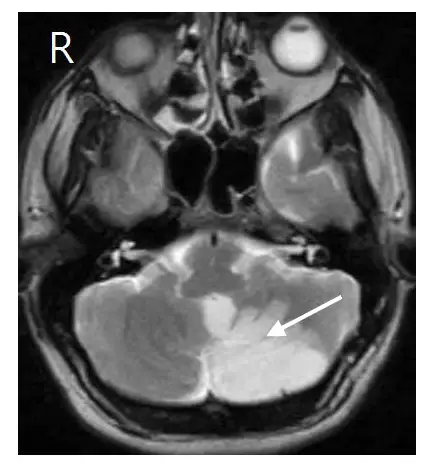

腦梗塞患者在 T2WI 核磁共振影像中發現如箭頭指出的白色陰影,患者最有可能會有下列那一種臨床症狀?

- 影像判讀:在 MRI T2WI(T2加權影像)中,液體或水腫呈現高訊號(白色)。腦梗塞(Stroke)急性期因細胞毒性水腫,在 T2WI 上會呈現白色高訊號區。

- 切面與加權:這是一張腦部**軸狀面(Axial view)**的 T2WI MRI 影像(腦脊髓液與病灶處呈現高亮白色)。

- 影像左上角標示了 "R",這代表影像的該側(左側)對應病人的右側(Right)。這是放射影像的標準慣例(如同從病人腳底往上看,影像左側=病人右側,影像右側=病人左側)。

- 白色箭頭指向影像的右半部,根據上